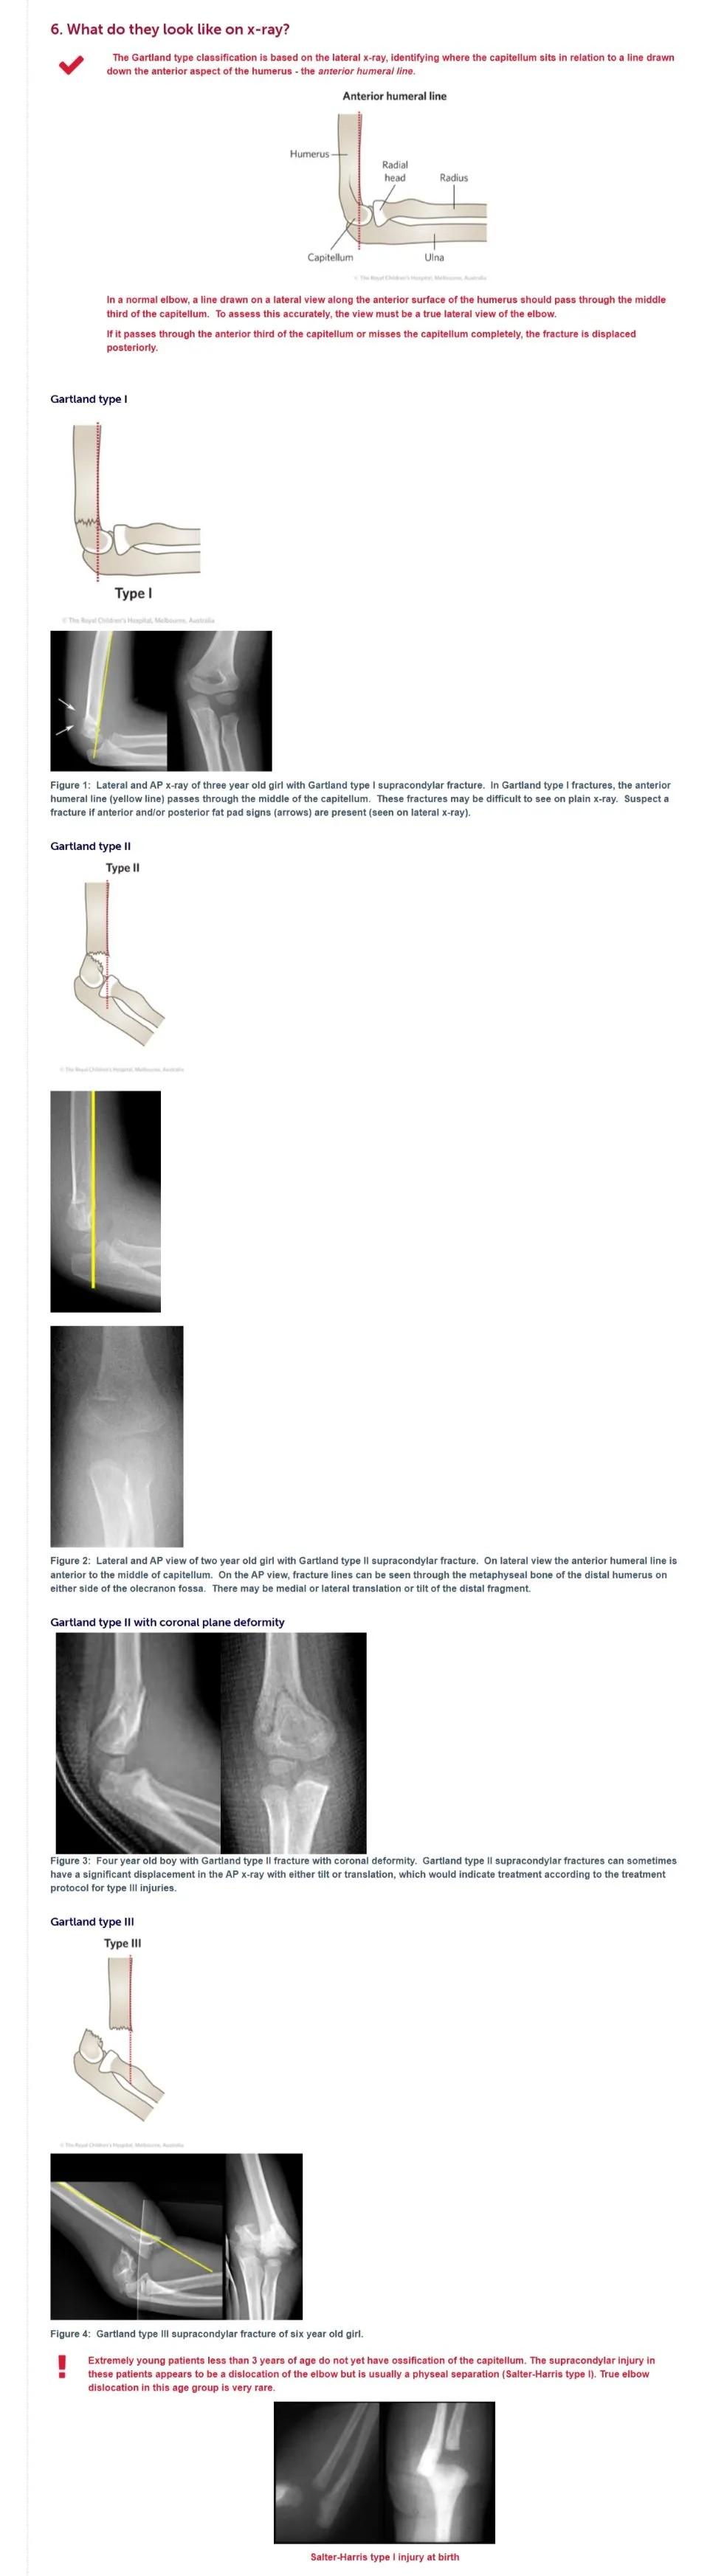

Can Gartland type II supracondylar fractures with coronal plane deformity be reduced by a general practitioner in the ED?

Can <b>Gartland type II</b> supracondylar fractures with <b>coronal plane deformity</b> be <u>reduced</u> by a general practitioner in the ED?<br><br>{{c1::No}}